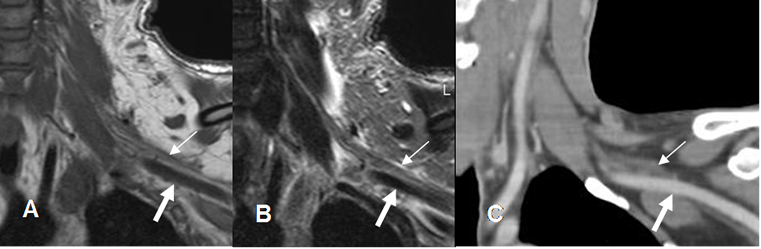

Fig 4. Raíces normales.

A: RM coronal en T1, B: RM coronal en T2 y C: TAC reconstrucción coronal. Raíces normales hipointensas, en la RM (Flechas delgadas), por encima de los vasos subclavios. (Flechas gruesas).

Fig 5. Raíces normales.

A: RM sagital en T1 y B: RM sagital en T2. Raíces normales (Flechas delgadas), por encima de los vasos subclavios. (Flechas gruesas).